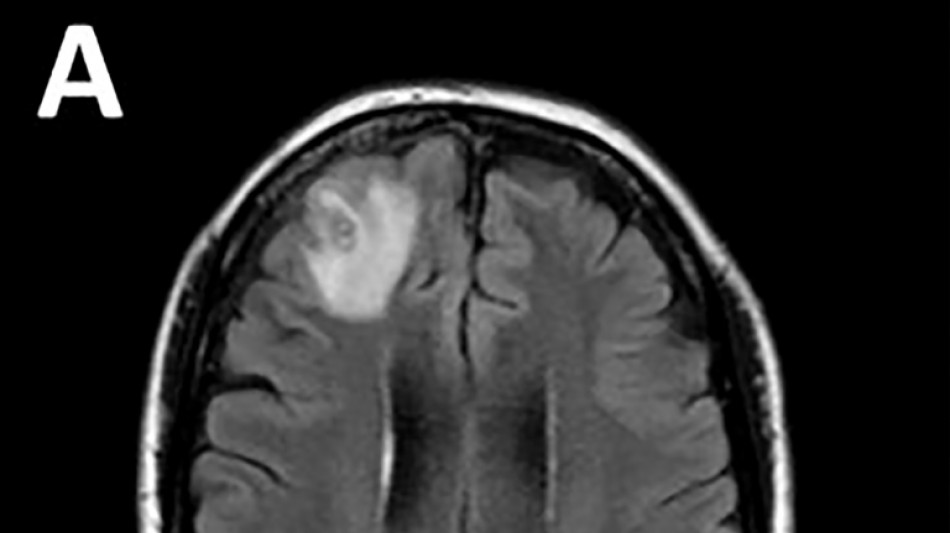

Les médecins ont découvert une "lésion atypique", grâce à un examen IRM, dans la partie frontale du cerveau de l'Australienne, âgée de 64 ans, qui souffrait de pertes de mémoire.

Le parasite, dont la "structure en forme de fil" est apparue sur les scanners cérébraux, a ensuite été identifié grâce à des tests ADN.